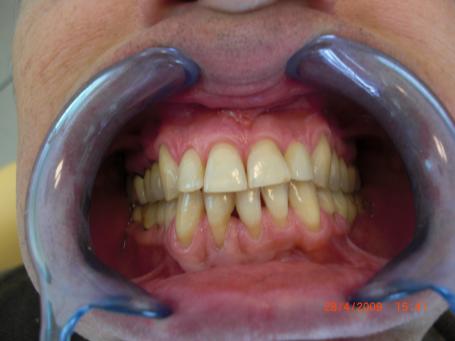

1°)Photo préopératoire.

On note la présence d'une couronne dentaire iatrogène en haut à droite. Cette couronne antérieure inesthétique laisse entrevoir le liseré métallique de l'armature métallique de cette couronne.

Cette infiltration est à la porte d'entrée aux bactéries qui sont à l'origine d'une éventuelle infection dentaire.